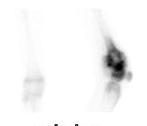

Sarcome d’Ewing

Le sarcome d’Ewing a été décrit la première fois en 1921 par James Ewing, cancérologue américain. C’est une tumeur osseuse à cellules rondes indifférenciées, plus précisément une tumeur neurœctodermique primitive. Il s’agit d’une tumeur extrêmement agressive, mais qui est très sensible à la radiothérapie. Il y aurait une translocation, c’est-à-dire une cassure ou une mutation dans les chromosomes 11 et 22. La maladie se localise principalement à la diaphyse de l’os long et parfois dans les vertèbres. La prédisposition serait 10 fois plus élevée chez les individus de race blanche plutôt que dans la population afro-américaine. Les données démographiques démontrent que ce sont les enfants qui sont les plus touchés ou les jeunes adolescents/adultes entre 5 et 20 ans, et il est extrêmement rare que ce cancer touche les gens au-delà de 20 ans. La prévalence est plus forte chez les garçons que chez les filles, et celles-ci ont de meilleurs taux de survie. Sur le plan radiographique, on décrit l’image du sarcome d’Ewing comme un « bulbe d’oignon », et la diaphyse est plutôt boursoufflée. Sur la scintigraphie osseuse (figure 1 ), la lésion apparaîtra plus

Antérieur

Postérieur